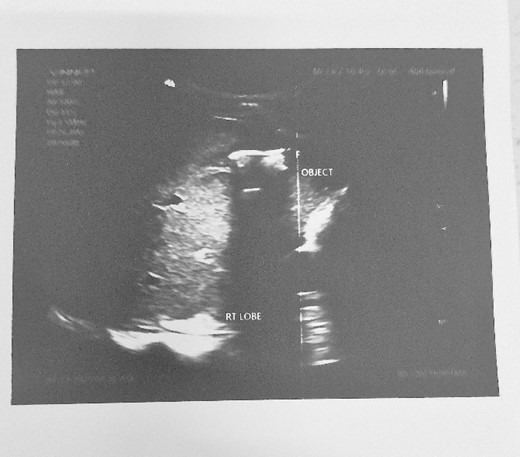

HB 9.9 mg/ml, sodium 135 mmol/L, chlorine 103 mmol/L, potassium 3.8 mmol/L, urea 4.3 mmol/L, and creatinine 108.5 umol/L. During the erect chest X-ray, the medical team observed the head of the spear within the abdominal cavity (Fig. 2), and a lateral chest X-ray confirmed its position in an ascending orientation (Fig. 3). The abdominal ultrasound showed the presence of a foreign body with an acoustic shade inside the liver parenchyma (Fig. 4); no free fluid was found in the Morrison’s pouch, but about 90 ml of free fluid was shown in the Douglass pouch. Both pleural spaces were free of fluid and had no pericardial fluid. We evaluated and discussed the possibility of performing an abdominopelvic computed tomography, but it was not feasible due to the patient's financial constraints.

Abdominal ultrasound showing an object with an acoustic shade inside the liver parenchyma.